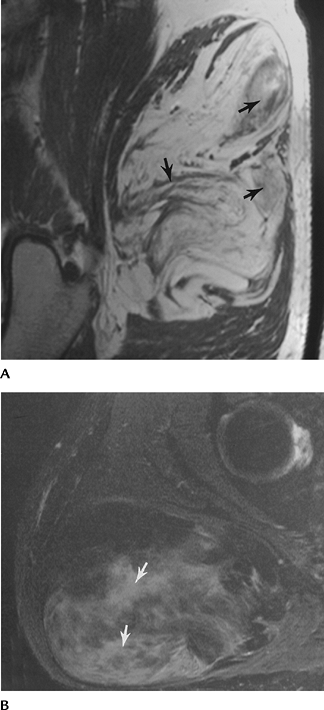

FIGURE 4-22 Axial (A) and sagittal (B) T2-weighted images of a Grade 1–2 strain of the hamstring muscles (arrows).

FIGURE 4-23 Coronal (A) and axial (B) T2-weighted images of an adductor muscle tear (arrows) with a central hematoma.